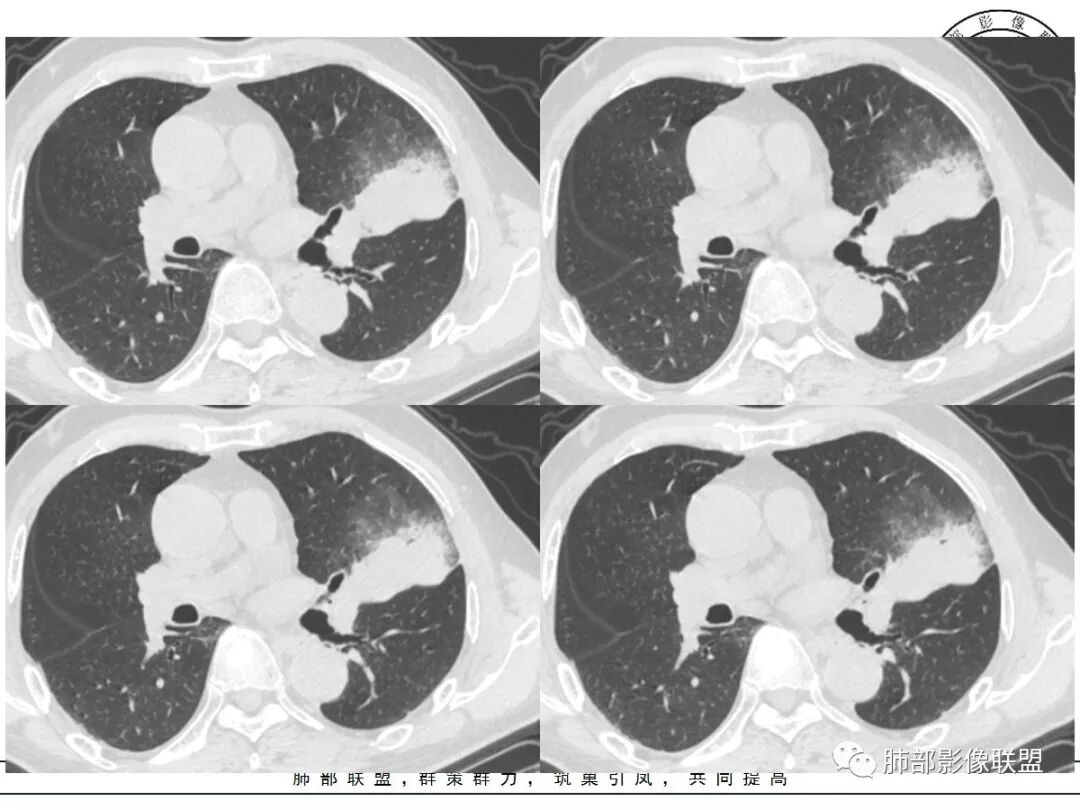

左肺上叶类圆形软组织影,边界较清楚,其内密度均匀,外侧缘可见空气新月征,并可见点状钙化,增强扫描可见均匀强化,病灶周围可见磨玻璃渗出性密度影,斜裂侧光滑平整。考虑炎性病灶,以肉芽肿性炎症为主(如真菌性肉芽肿),鉴别结核(无卫星灶,无多态性),肺癌(无毛刺,分叶等恶性征象,)细菌性炎症(密度一般不这么致密,很少钙化及空气新月征)。

左肺上叶类圆形软组织影,界清,内见空洞影,病灶周围斑片影,可见空气支气管征,未垮叶。考虑炎性病变,糖尿病四大金刚,肺克?毛霉?

老年男性,血糖升高六年,反复咳痰咳嗽3周,左肺上叶近斜裂类圆形肿块影,边缘伴磨玻璃影,边界不清。内部可见支气管走行、钙化、小空洞,叶间裂局部膨隆,增强扫描轻度强化,内部可见小的低密度区,边界尚清。考虑为炎性病变可能性大。

左肺叶裂旁实变影,宽基底与叶裂胸膜相连,边缘平直,部分略膨隆,病灶近段及上段支气管深入病灶内,部分壁略增厚,远端支气管截断,似有小空泡,壁规则,内部可见高密度钙化,周围可见模糊的GGO,血象正常,考虑结核(NTM),鉴别隐球菌,奴卡,放线菌。

老年男性,66,反复咳嗽、咳痰3月。糖尿病,血象不高。

胸部CT:左肺上叶类圆形肿块影,边界较清楚,密度较均匀,内可见小片坏死、偏心空洞、空气新月征、点状钙化,周围晕、絮状渗出、边缘模糊,支气管扩张、充气征、支气管进入病灶堵塞,叶裂牵拉明显,增强扫描中度均匀强化,纵隔可见淋巴结。考虑:炎性病灶,肉芽肿性炎症,曲霉?毛霉?鉴别:TB,淋巴瘤。

左上肺类圆形肿块影,边界较清楚,支气管通畅略扩张,周围磨玻璃影,其内密度均匀,外侧见空气新月征,且见点状钙化。叶间裂光滑稍膨隆。老年男性,糖尿病,高血压,痰培养克雷伯菌。综合考虑炎性病灶,克雷伯合并真菌感染,曲霉。结核合并真菌。鉴别肺癌合并感染。

左肺上叶类圆形软组织影,边界稍模糊,其内密度均匀,外侧缘可见空气新月征,并可见点状钙化,增强扫描渐进性强化,病灶周围可见磨玻璃影,斜裂侧光滑平整,气管未见明显闭塞,淋巴结未见肿大,糖尿病患者,首先考虑感染性变,结核并曲霉?